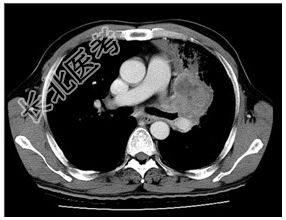

- [材料题] 患者,男性,58岁。咳嗽咳痰1月余,间有血丝痰。无发热及胸痛。查体.锁骨上可扪及肿大淋巴结。左上肺呼吸音稍弱,双肺未闻及干湿性啰音。心脏无异常。行胸部CT增强扫描。